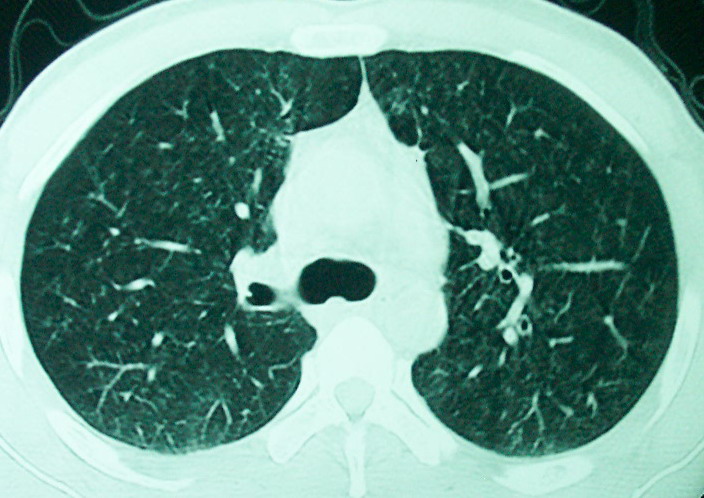

m      37y      发热   咳脓痰月余      ct肺脓肿但住院抗炎治疗后双肺内结节不知该如何解释

治疗后见左肺下野病灶较前缩小但双肺内结节影似无变化请较各位老师该如何下结论    治疗前wbc14.5 治疗后wbc 11.0

如果你仔细的同层面对比,你会发现所有的病灶均有比较明显的吸收、缩小。病变的形态,特别是脓肿的形态、壁的厚薄、内壁均有很大的变化,均在往好的方面发展。与临床症状、血像均符合,治疗效果比较显著,就是肺脓肿并双肺的化脓性炎症灶。